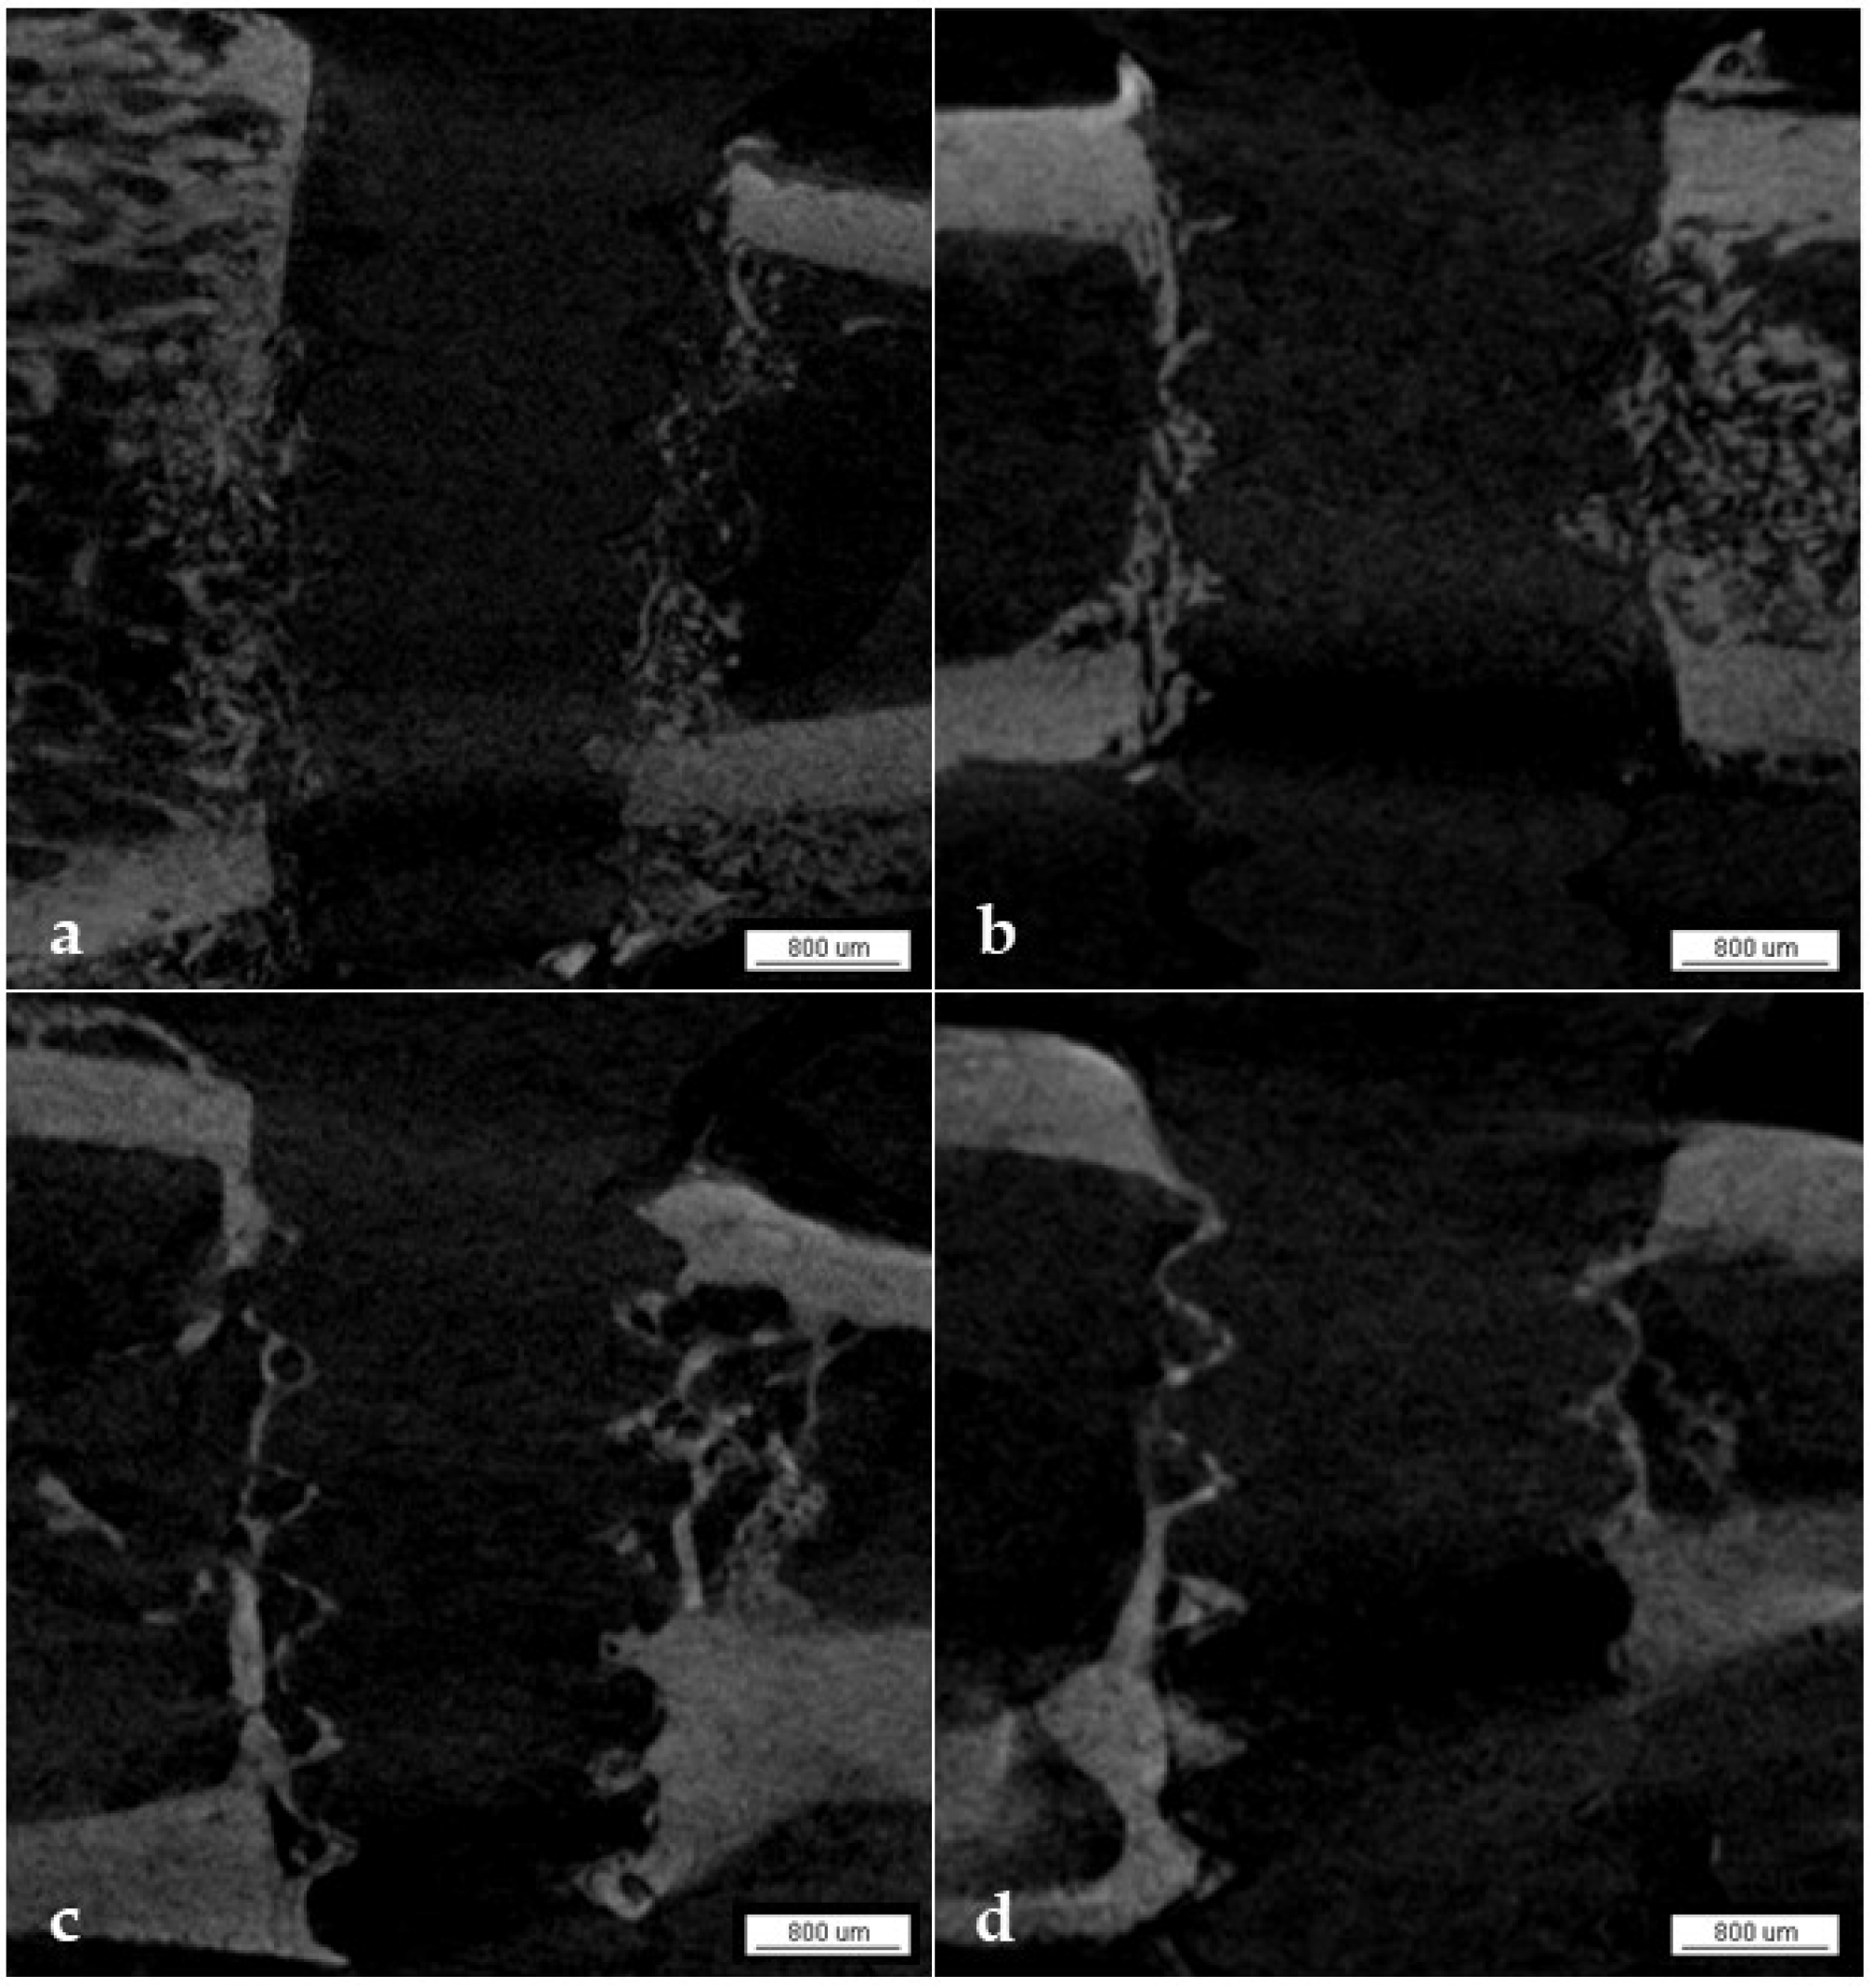

3.1.6. Qualitative Analysis